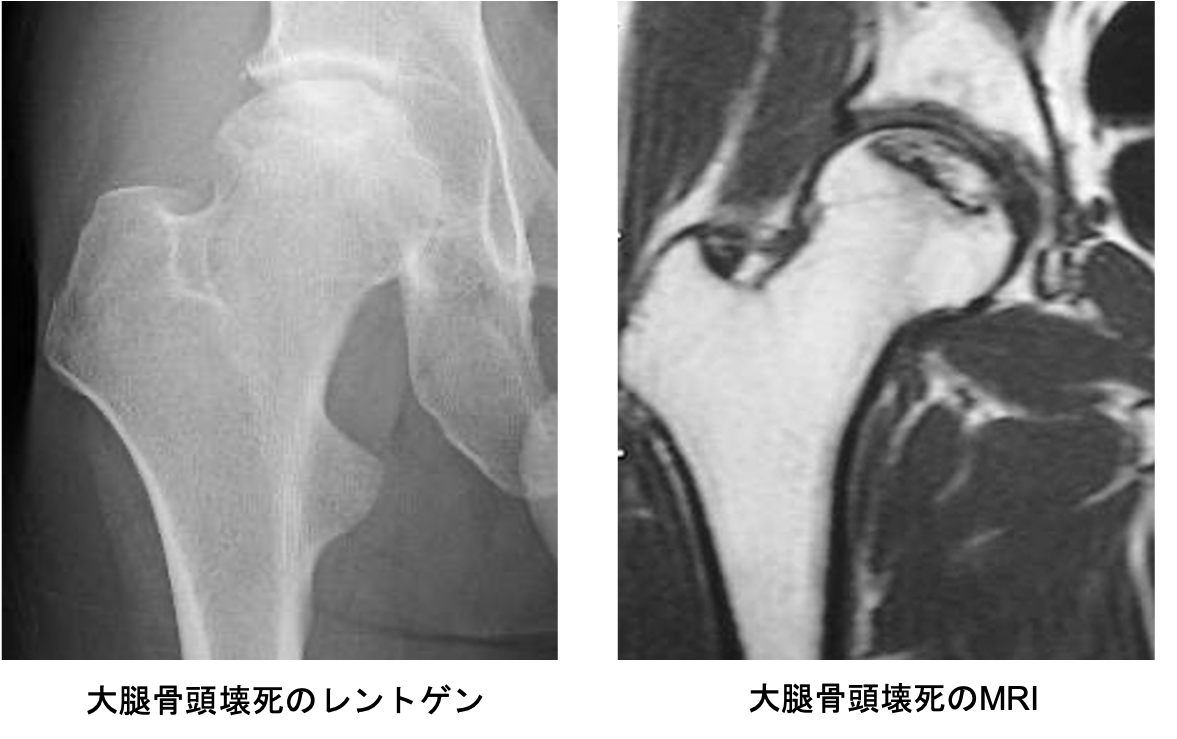

股関節の中心である大腿骨頭が壊死してつぶれるために痛みを生じる病気です。アルコールの多飲やステロイドの使用に関連しているとも言われていますが、いまだにはっきりしておらず国の難病に指定されています。進行すると大腿骨頭が陥没を起こし、歩行が困難になります。症状が強ければ人工股関節置換術が必要になることがあります。